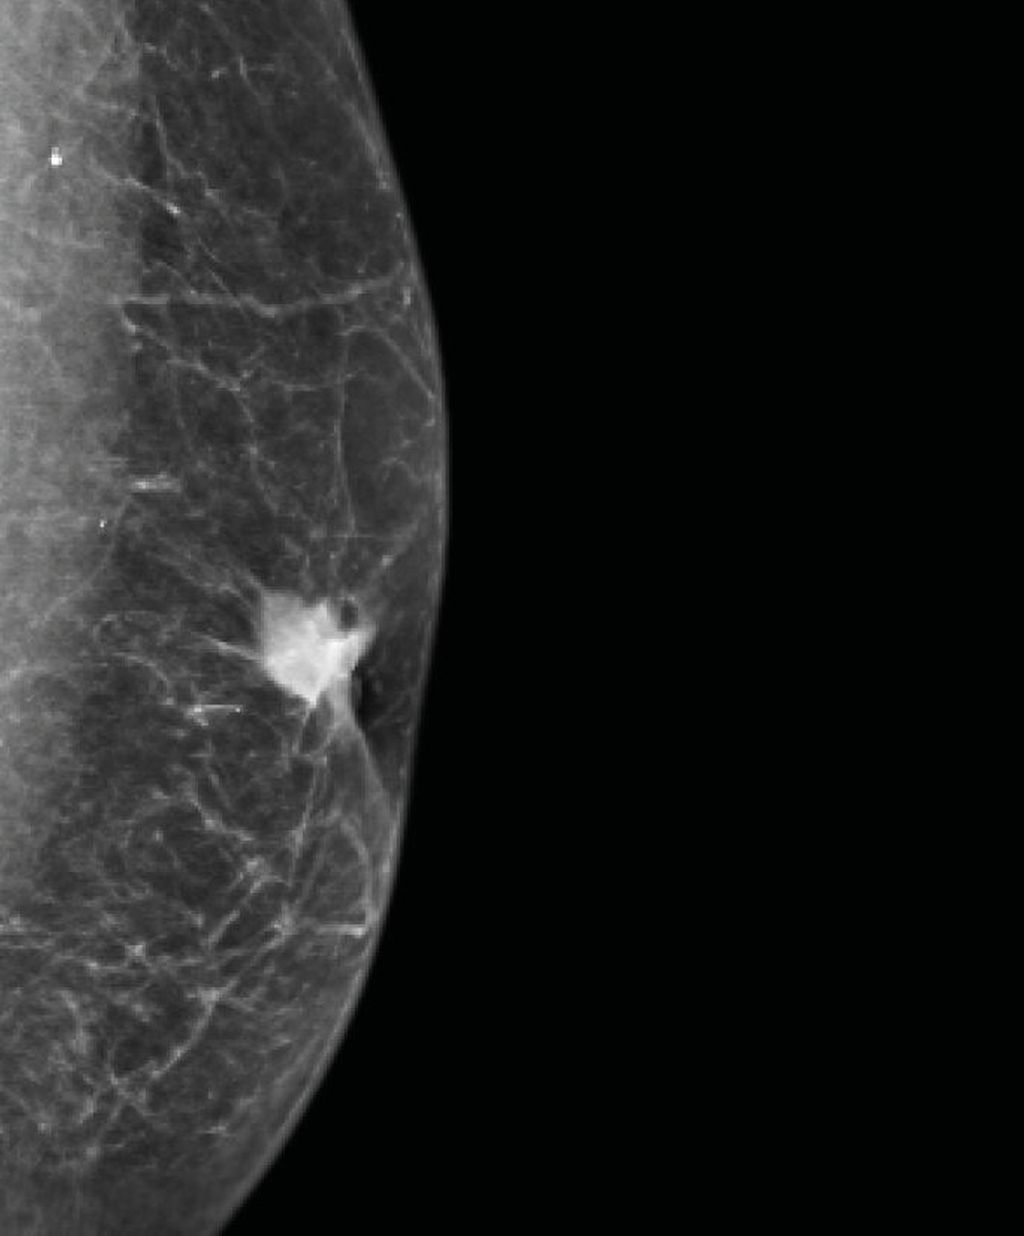

Prof. Exner befasste sich mit einem bei Ärzt:innen, Männern und der Bevölkerung allgemein noch immer wenig präsenten Thema: dem Brustkrebs beim Mann. Etwa 0,5–1% der Mammakarzinome betreffen Männer. Risikofaktoren sind vor allem höheres Alter, Rauchen, Alkoholabusus, Adipositas und eine genetische Disposition (v.a. BRCA1/2-Mutationen).1 Aufgrund des geringen Bewusstseins für die Krankheit erfolge die Diagnose meist erst spät (Abb.1). Zu diesem Zeitpunkt lägen in 30–40% der Fälle bereits Lymphknotenmetastasen vor, erklärte Exner. Diagnostik, Therapie und Nachsorge entsprechen den Maßnahmen bei postmenopausalen Frauen.1,2 Doch es gibt auch Unterschiede. So liegt beim Mann häufiger eine genetische Disposition vor und das Risiko für Zweitmalignome ist bis zu 20% höher als bei der Frau.1 Mehr als 90% der Männer hätten ein ER-positives, invasiv-duktales Karzinom,1 das sich meist als derber Tumor hinter der Brustwarze zeige (Abb.2), sagte Exner. Allerdings kämen auch andere Tumoren vor, etwa Sarkome.

Abb. 2: Bei Männern zeigt sich ein Mammakarzinom, so wie in dieser Mammografie, meist als derber Knoten hinter der Brustwarze